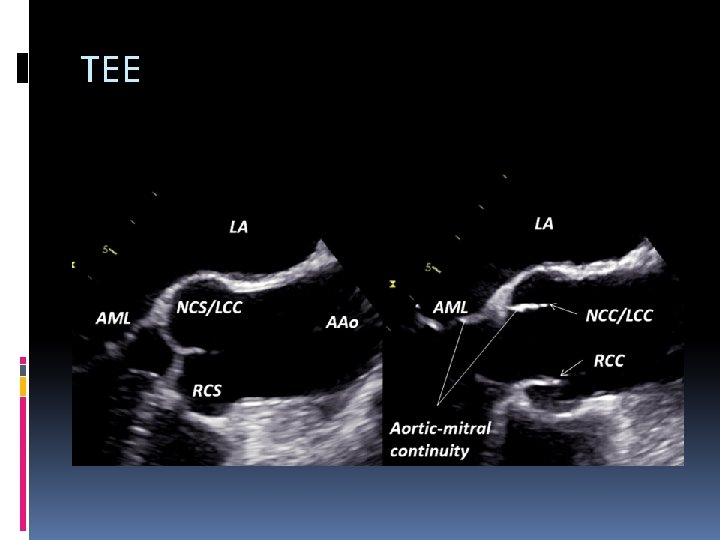

TEE